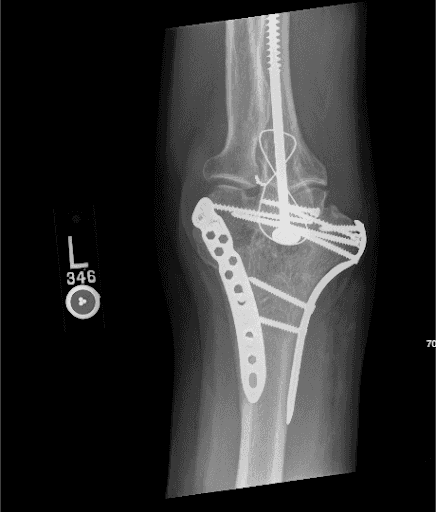

Imaging is essential to assess the integrity of the ORIF construct. Radiographs are done with lateral and slightly modified anteroposterior (AP) views. The AP view involves flexion of the elbow to about 40 degrees to allow the olecranon to move out of the way, allowing the distal humerus to be better visualized.6 There has been increasing interest in the use of computed tomography (CT) scans, particularly 3D reconstructions when there is articular involvement.11

Removal of the medial plate may not always be necessary; however, we felt that in this case the medial plate was quite prominent so its removal in the context of a healed fracture would help to relieve some of the patient’s symptoms. Pre-op x-rays are included The creation of an adipofascial sleeve around the transposed nerve we believe helps the nerve glide easily as the patient moves the upper limb and prevents recurrent nerve compression from scarring and fibrosis. The technique, in brief, is thus described here. A posteromedial incision is made over the medial epicondyle and extended 8–10 cm proximally and 4–5 cm distally. The ulnar nerve is identified proximally, just posterior to the medial intermuscular septum, after careful blunt dissection. It is then further dissected in an antegrade fashion taking care to keep the vascular supply of the epineurium intact. After the nerve is mobilized and transposed anteriorly, attention is turned to the adipofascial flap. The flap, with vascular supply in place, is carefully wrapped posterior-to-anterior and sutured to create a tunnel that surrounds the entire nerve length. Finally, ranging of the elbow is done to ensure the nerve is not kinked. This technique has been well-described in the literature with specific application in cases like this one.12–14

Figure 1. AP view of the Left elbow x-ray showing the position of the plates pre-op.